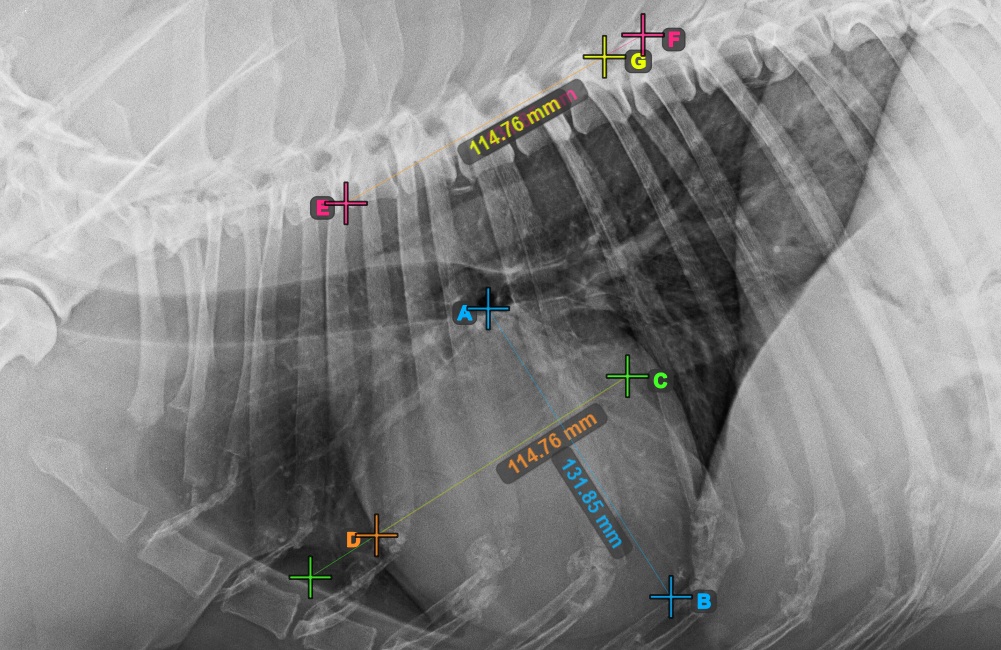

Continue the measurement by marking the widest right (cranial) point of the short axis of the heart.

The image below represents a typical placement of the most cranial point on the short axis of the heart.

../../_images/image395.jpg

Complete the short axis of the heart by marking the widest left (caudal) point.

The image below represents the typical placement of the most caudal point on the short axis of the heart.

../../_images/image396.jpg